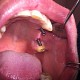

Dr. Daniela Alexandru (implantologie, protetica, chirurgie dentoalveolara)

Cum sa descoperim singuri caria dentara ?

Caria dentara este un proces distructiv cronic al tesuturilor dure ale dintelui, fara caracter inflamator, producând necroza si distructia acestora, urmate de cavitatie coronara sau radiculara. Caria se dezvolta numai pe dintii în contact...